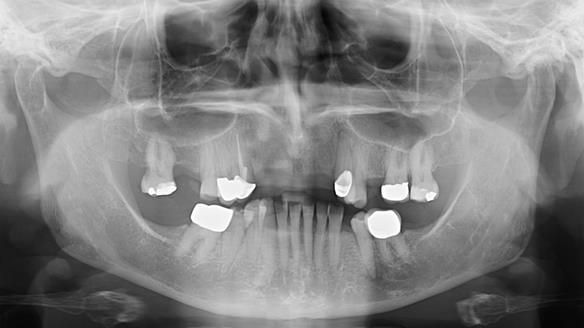

- Diagnosis and plan – Flexible upper denture ill-fitting with poor stability, retention, and appearance. Plan: metal-based upper partial denture/splint with lighter porcelain-bonded-to-zirconia crowns on UR3 and UL3.

- Metalwork framework try-in – to verify fit, path of insertion, and support.